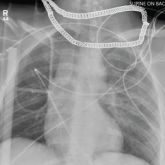

ArticleCross at the Green, Not in BetweenAuthor:Nanda R. Hichkad, PA-C, MMScPublish date: September 23, 2019While riding his bicycle, a 25-year-old man tried to cross a busy intersection and was hit by a car. What does an x-ray reveal?Read More